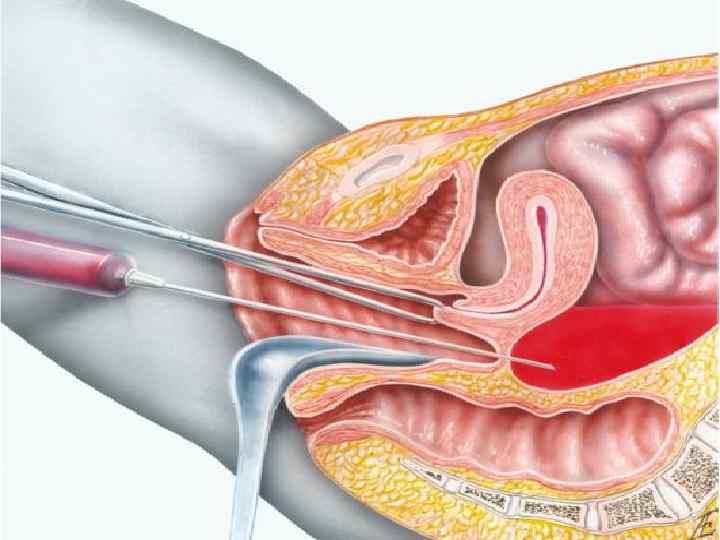

Инструментальная и лабораторная диагностика Определение уровня ХГ (при подозрении на внематочную беременность) УЗИ органов малого таза Пункция прямокишечно маточного углубления: обнаружение свободной крови в брюшной полости КТ Лапароскопия